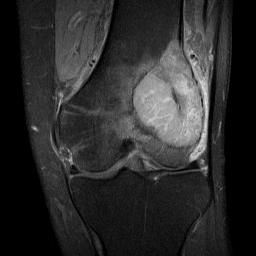

MRI

Low signal intensity T1 / high signal intensity T2

Areas of ABC seen in 10 - 14%

Look for signs of grade III: soft tissue extension